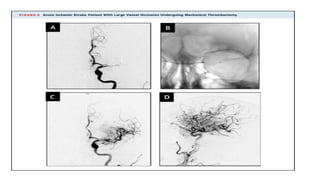

MR CLEAN trial

MR CLEAN TRAIL

• (Multicenter Randomized Clinical Trial of Endovascular Treatment for Acute Ischemic Stroke in

the Netherlands) randomized acute stroke patients presenting within 6 h of stroke onset to standard

medical management alone or standard medical management followed by MT.

• Noninvasive vascular imaging before enrolling a patient into MT was mandatory, and as long as

there was clear vessel occlusion.

• Patients with AIS who were older than 18 years of age and with anterior circulation LVO

confirmed on noninvasive vascular imaging were eligible to be enrolled in the trial.

• Good FIO was superior among those treated with the combination of MT and standard medical

management

• There were no significant differences in mortality or occurrence of sICH.